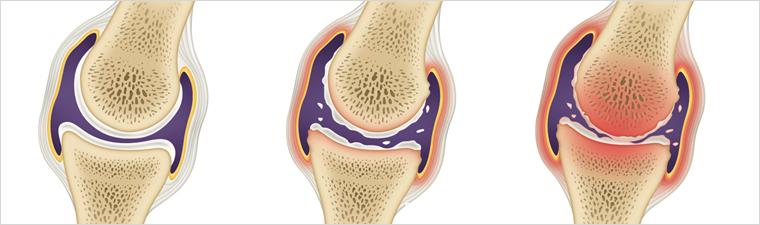

연골이 닳으면서 관절 사이 간격이 줄어들고 통증과 강직이 나타납니다. 초기에는 소염진통제나 연골 보호제, 휴식과 적절한 운동으로 경과를 관찰하며 보존적 치료를 시도합니다. 보존적 치료로 증상이 호전되지 않거나 기능 저하가 심하면 수술적 치료를 고려할 수 있습니다.

주로 퇴행성 변화로 인해 나타나는 증상입니다. 관절 사이의 연골이 닳아 없어지면 관절 내부와 주변에 염증이 생겨 뻐근함과 통증을 유발합니다. 골반 아래쪽에서 불편감이 생기고, 양반다리 자세에서 통증이 심해지며 계단 오르기나 장거리 보행 시 증상이 악화됩니다.

연골 보호층이 닳아 없어지면 뼈와 인대에 손상이 발생하고 염증과 만성 통증이 생깁니다. 연골 손상으로 인한 통증은 회복이 더디므로 조기 관리가 필요합니다.